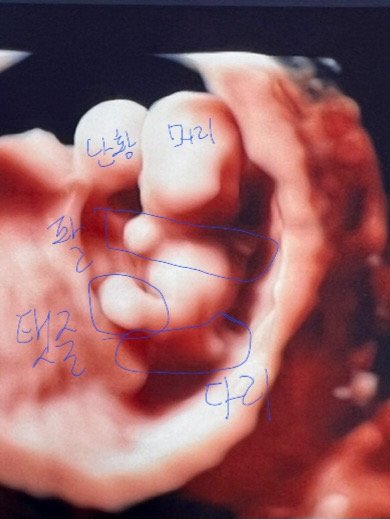

9์ฃผ0์ผ ๐ป์ ค๋ฆฌ๊ณฐ๐ป์์ โจ

9์ฃผ์ฐจ. ์ด๊ฑฐ ์ ค๋ฆฌ๊ณฐ ๋ง์ฃ ?? ์ฌ์ฅ์๋ฆฌ๋ ๋ ์ปค์ง๊ณ ๋จธ๋ฆฌ,ํ,๋ค๋ฆฌ๋ ๊ตฌ๋ถ๋๋ ์กฐ๊ธ์ฉ ์ค๊ฐ๋ฉ๋๋ค๐ง๐ปโโ๏ธ (์๋ ์ 6์ฃผ์ฐจ์ ๊ณ๋ฅ์ ์ฐํด์ ์ด๋ ๊ฒ ์๊ธฐํํ๋งํผ ์ฑ์ฅํ ๊ฑฐ ์ฒ์ ๋ณด๊ฑฐ๋ ์ใ ใ ) ๋ค๋ค ๊ฑด๊ฐํ ์๊ธฐ ๋ง๋๊ณ ์ค์ธ์